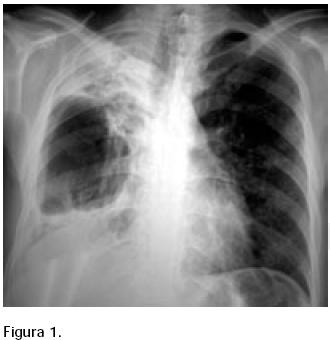

Masculino de 30 años, originario de Tijuana, toxicómano (marihuana y metanfetaminas), alcohólico, seronegativo para el virus de la inmunodeficiencia humana (VIH). Actualmente, reside en un centro comunitario de rehabilitación. En febrero de 2004 se diagnosticó tuberculosis por baciloscopia y se inició con esquema primario (rifampicinaisoniacida, pirazinamida y etambutol y, posteriormente, rifampicinaisoniacida). Sus baciloscopías se reportaron persistentemente positivas y el paciente continuó con tos pertinaz y disnea de mínimo esfuerzo. Se refirió a la Clínica de Tuberculosis en enero de 2005. Sus radiografías torácicas mostraron deterioro progresivo con extensa destrucción del lóbulo superior derecho y paquipleuritis ipsilateral (Figura 1).

Se suspendió el tratamiento y se realizó cultivo de expectoración (BACTEC) reportándose aislamiento de Mycobacterium avium complex en marzo de 2005; se inició tratamiento con claritromicina (1 g/día) y amikacina (15 mg/kg tres veces a la semana). Su evolución clínica ha sido favorable; sus baciloscopías y cultivo se han negativizado.